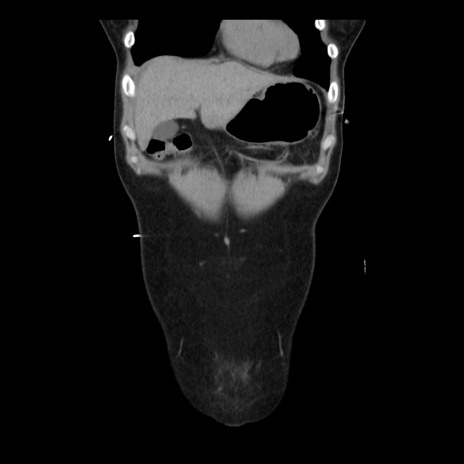

症例10(冠状断像)

【症例】 50歳代女性

【主訴】 腹痛

【現病歴】前日生レバーを食べた。今朝に排便あり。 昼前に突然発症の腹痛を生じ、当院救急外来を受診した。

【既往歴】 子宮筋腫にてで子宮全摘後

【身体所見】 意識清明、腹部:平坦、軟、下腹部やや左を中心に圧痛・反跳痛あり、筋性防御あり

【データ】WBC 7800、CRP 0.07